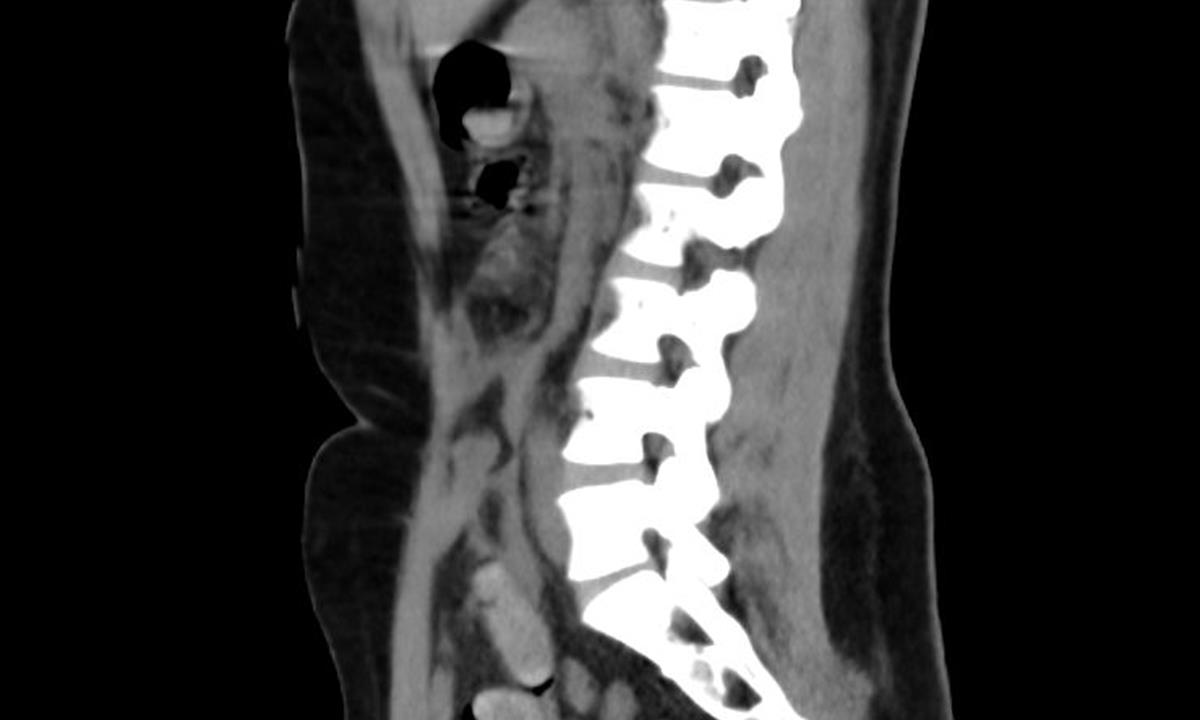

O víkendu odhalili celníci na pražském letišti Václava Havla v Ruzyni polykače kokainu. Jednalo se o 35letou cizinku, která postupně vyloučila 11 kapslí obsahujících drogy. Cizinka cestovala na pravidelné lince Madrid-Praha.

Ke kontrole byla polykačka celníky vytipována na základě provedené rizikové analýzy daného letu. Prvotní podezření na pašování drog celníkům potvrdily kontrolní stěry z rukou pašeračky.

Postupně z těla pašeračky vyšlo 11 kontejnerků naplněných bílým práškem. Jeden o váze 116,3 gramů byl ukryt v pohlavním ústrojí ženy. Chemická látka při provedení detekční zkoušky pozitivně reagovala jako kokain. Celková hmotnost všech kapslí včetně drogy je více než 230 gramů. Určení vlastní hmotnosti a druhu zajištěné drogy je předmětem další odborné expertízy. Podle zkušeností celníků se s největší pravděpodobností jedná o velmi koncentrovaný kokain. Zda byla droga určena na český trh nebo k distribuci v jiné zemi, je předmětem dalšího šetření.